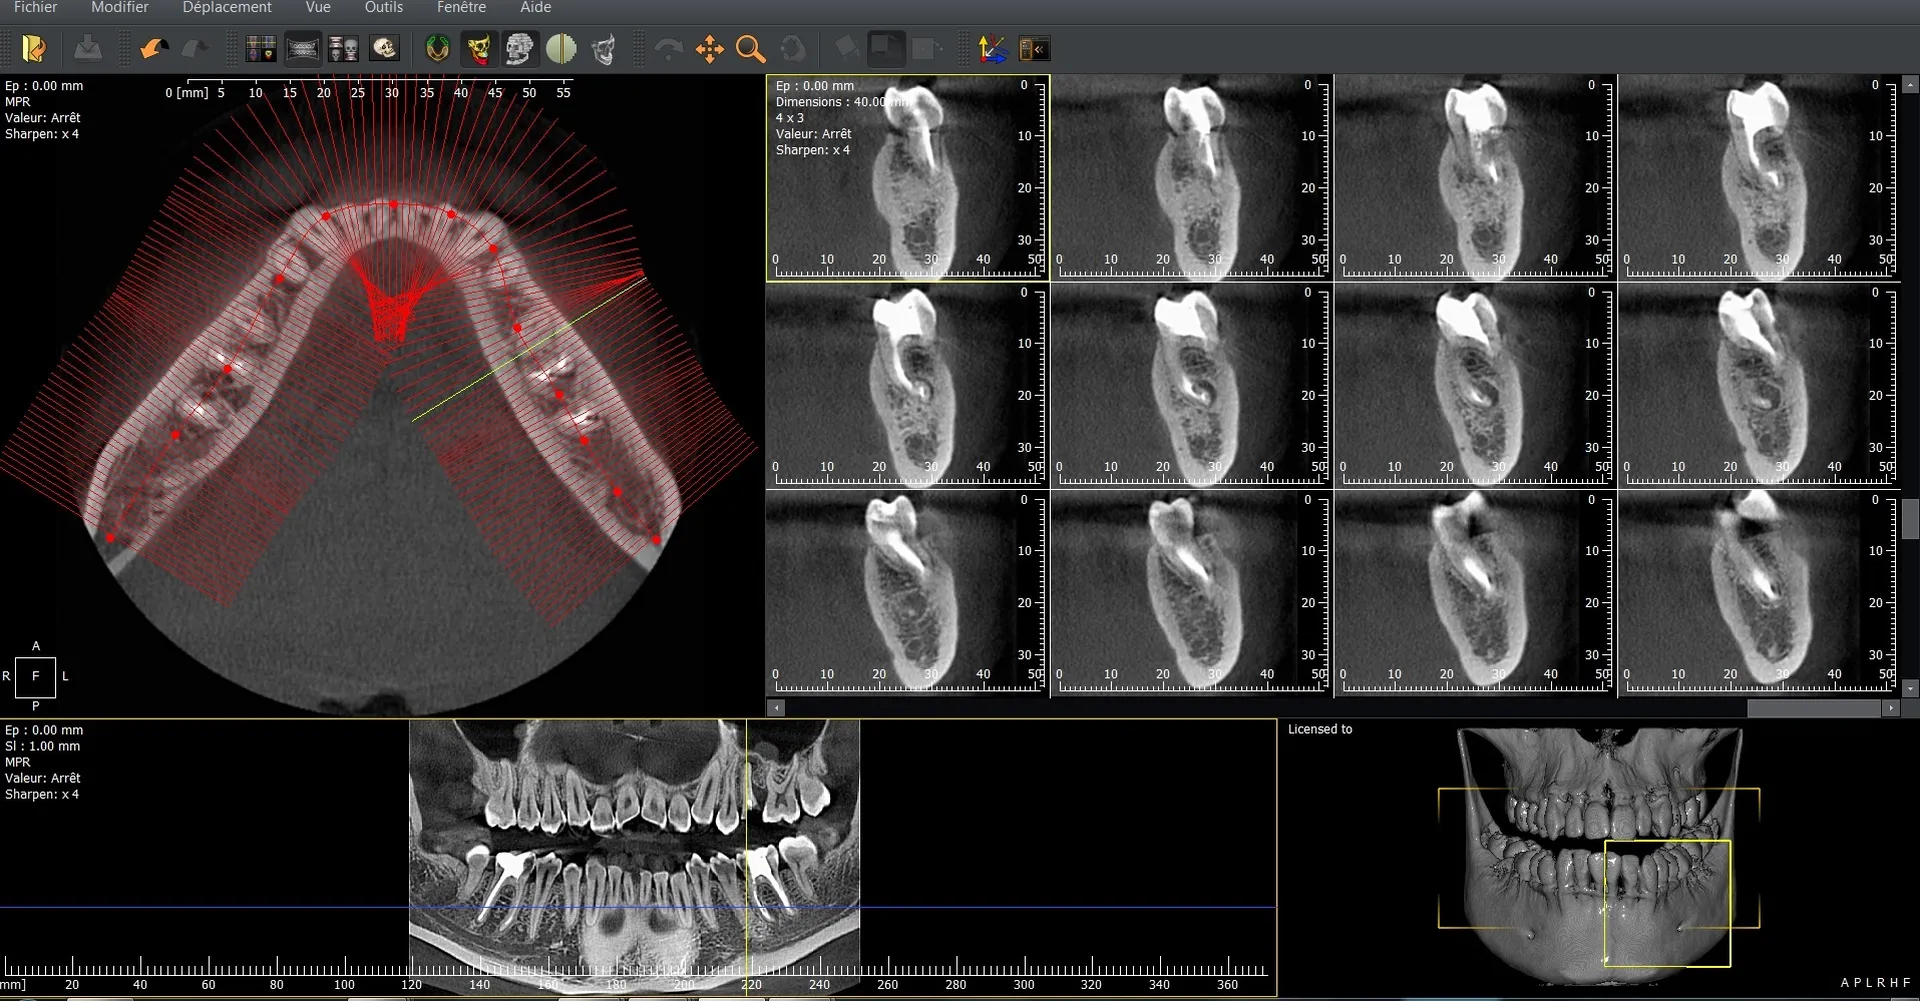

L’I-Max 3D XPRO est un système Cone Beam multifonction 4-en-1 conçu pour fournir une imagerie dentaire ultra-précise dans divers modes : panoramique, 3D, céphalométrie et scan d’objets (modèles en plâtre, porte-empreintes).

La qualité d’image est exceptionnelle, avec une résolution de 70 microns, assurant une finesse diagnostique accrue.

Le champ d’imagerie (FOV) peut être ajusté entre 16×11 cm à 5×5 cm, ce qui permet de cibler précisément la zone d’intérêt et de limiter l’exposition aux rayonnements.

La technologie Super IGZO est au cœur de ce système, avec des innovations telles que le traitement IA (algorithmes de débruitage), le Focus Scintillator pour réduire le bruit et l’algorithme AutoMAR pour atténuer les artéfacts métalliques.  Le positionnement "face à face" améliore le confort du patient et la reproductibilité des prises de vue.

Grâce à sa compacité (empreinte au sol inférieure à 1 m²) et son installation murale ou en colonne, l’appareil peut s’adapter aux contraintes d’espace des cabinets.  L’interface est intuitive, facilitant le passage entre les modes 2D et 3D, et la planification implantaire est supportée par le logiciel QuickVision 3D intégré pour visualiser, simuler et guider les interventions.